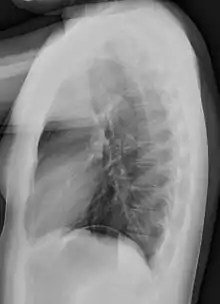

A chest radiograph, called a chest X-ray (CXR), or chest film, is a projection radiograph of the chest used to diagnose conditions affecting the chest, its contents, and nearby structures. Chest radiographs are the most common film taken in medicine.

Like all methods of radiography, chest radiography employs ionizing radiation in the form of X-rays to generate images of the chest. The mean radiation dose to an adult from a chest radiograph is around 0.02 mSv (2 mrem) for a front view (PA, or posteroanterior) and 0.08 mSv (8 mrem) for a side view (LL, or latero-lateral).[1] Together, this corresponds to a background radiation equivalent time of about 10 days.[2]